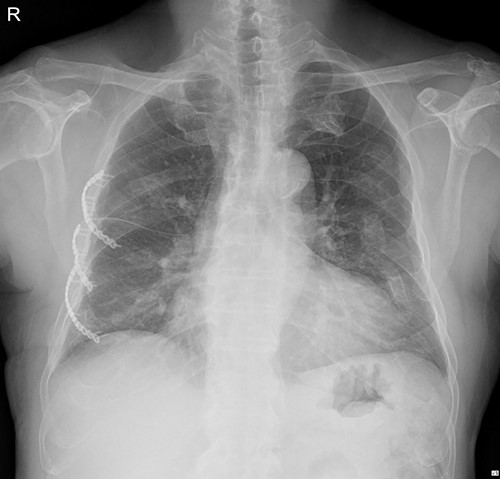

The patient visited the outpatient clinic on 07 March 2022, for stitches removal, complaining of mild discomfort on the operation site (Fig. 3.). Chest X-ray showed a large, localized submuscular emphysema between the rib cage and the SAM. The surgical wound was clear. Stitches were removed as planned, and the patient was asked to revisit the outpatient clinic 3 days later.